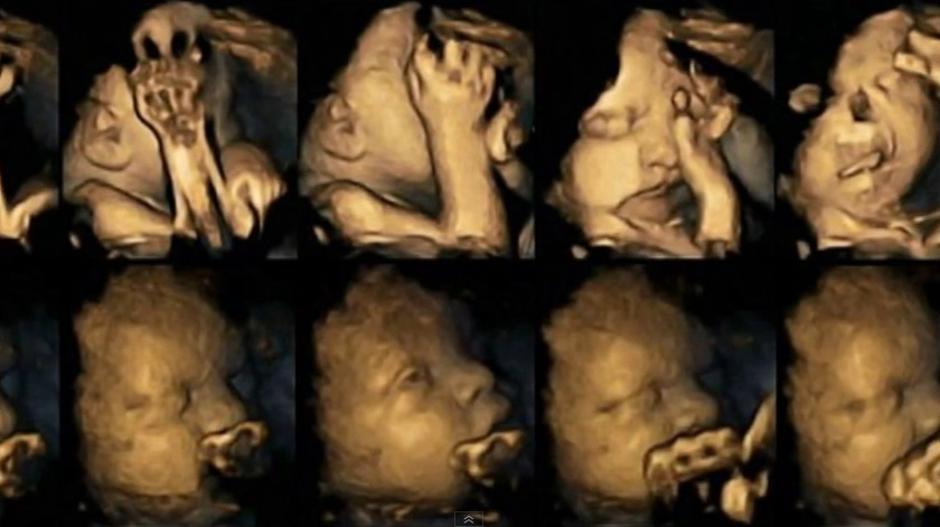

Ove 4D snimke otkrivaju kako pušenje utječe na bebe

Foto: screenshot/youtube

Znanstvenici sa Sveučilišta Durham proučavali su razlike između 20 majki koje ne puše i onih koje puše, a razvoj bebe su pratili 4D ultrazvukom u 24., 28., 32. i 36. tjednu trudnoće.

Otkriveno je da se bebe pušača češće dodiruju po licu i ustima u odnosu na bebe nepušača jer s vremenom dobivaju veću kontrolu nad pokretima, odnosno brže se razvijaju.

Otkriveno je da pušenje usporava razvoj živčanog sustava kod nerođenog djeteta te je njihova kontrola pokreta smanjena, piše Daily Mail.